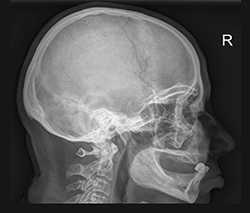

Рентгенография черепа

Рентген черепа – это метод лучевой диагностики, который применяется для исследования костей свода и основания черепа, костей лицевого скелета и головного мозга. Рентгенологическое исследование черепа помогает поставить диагноз, решить вопрос с выбором тактики лечения и проконтролировать динамику лечебного воздействия. Рентген черепа обычно выполняется в положении лежа или сидя с фиксированной с помощью специальных приспособлений головой. Врач может назначить исследование в одной или нескольких проекциях: правой боковой, левой боковой, переднезадней, заднепередней, аксиальной, полуаксиальной, прицельной. При этом потребуется снять все металлические аксессуары с шеи и головы.

Диагностика заболеваний черепа может включать различные виды рентгенографии, которые назначаются в зависимости от клинических проявлений и истории заболевания:

Обзорная рентгенография черепа проводится в обязательном порядке при травмах головы, с целью обнаружения переломов свода и основания черепа, смещения костных отломков. В случае высокой плотности костной ткани переломы могут быть не распознаны, поэтому рентгенологический метод уступает по точности и достоверности компьютерной томографии, но является более простым и быстрым способом диагностики.